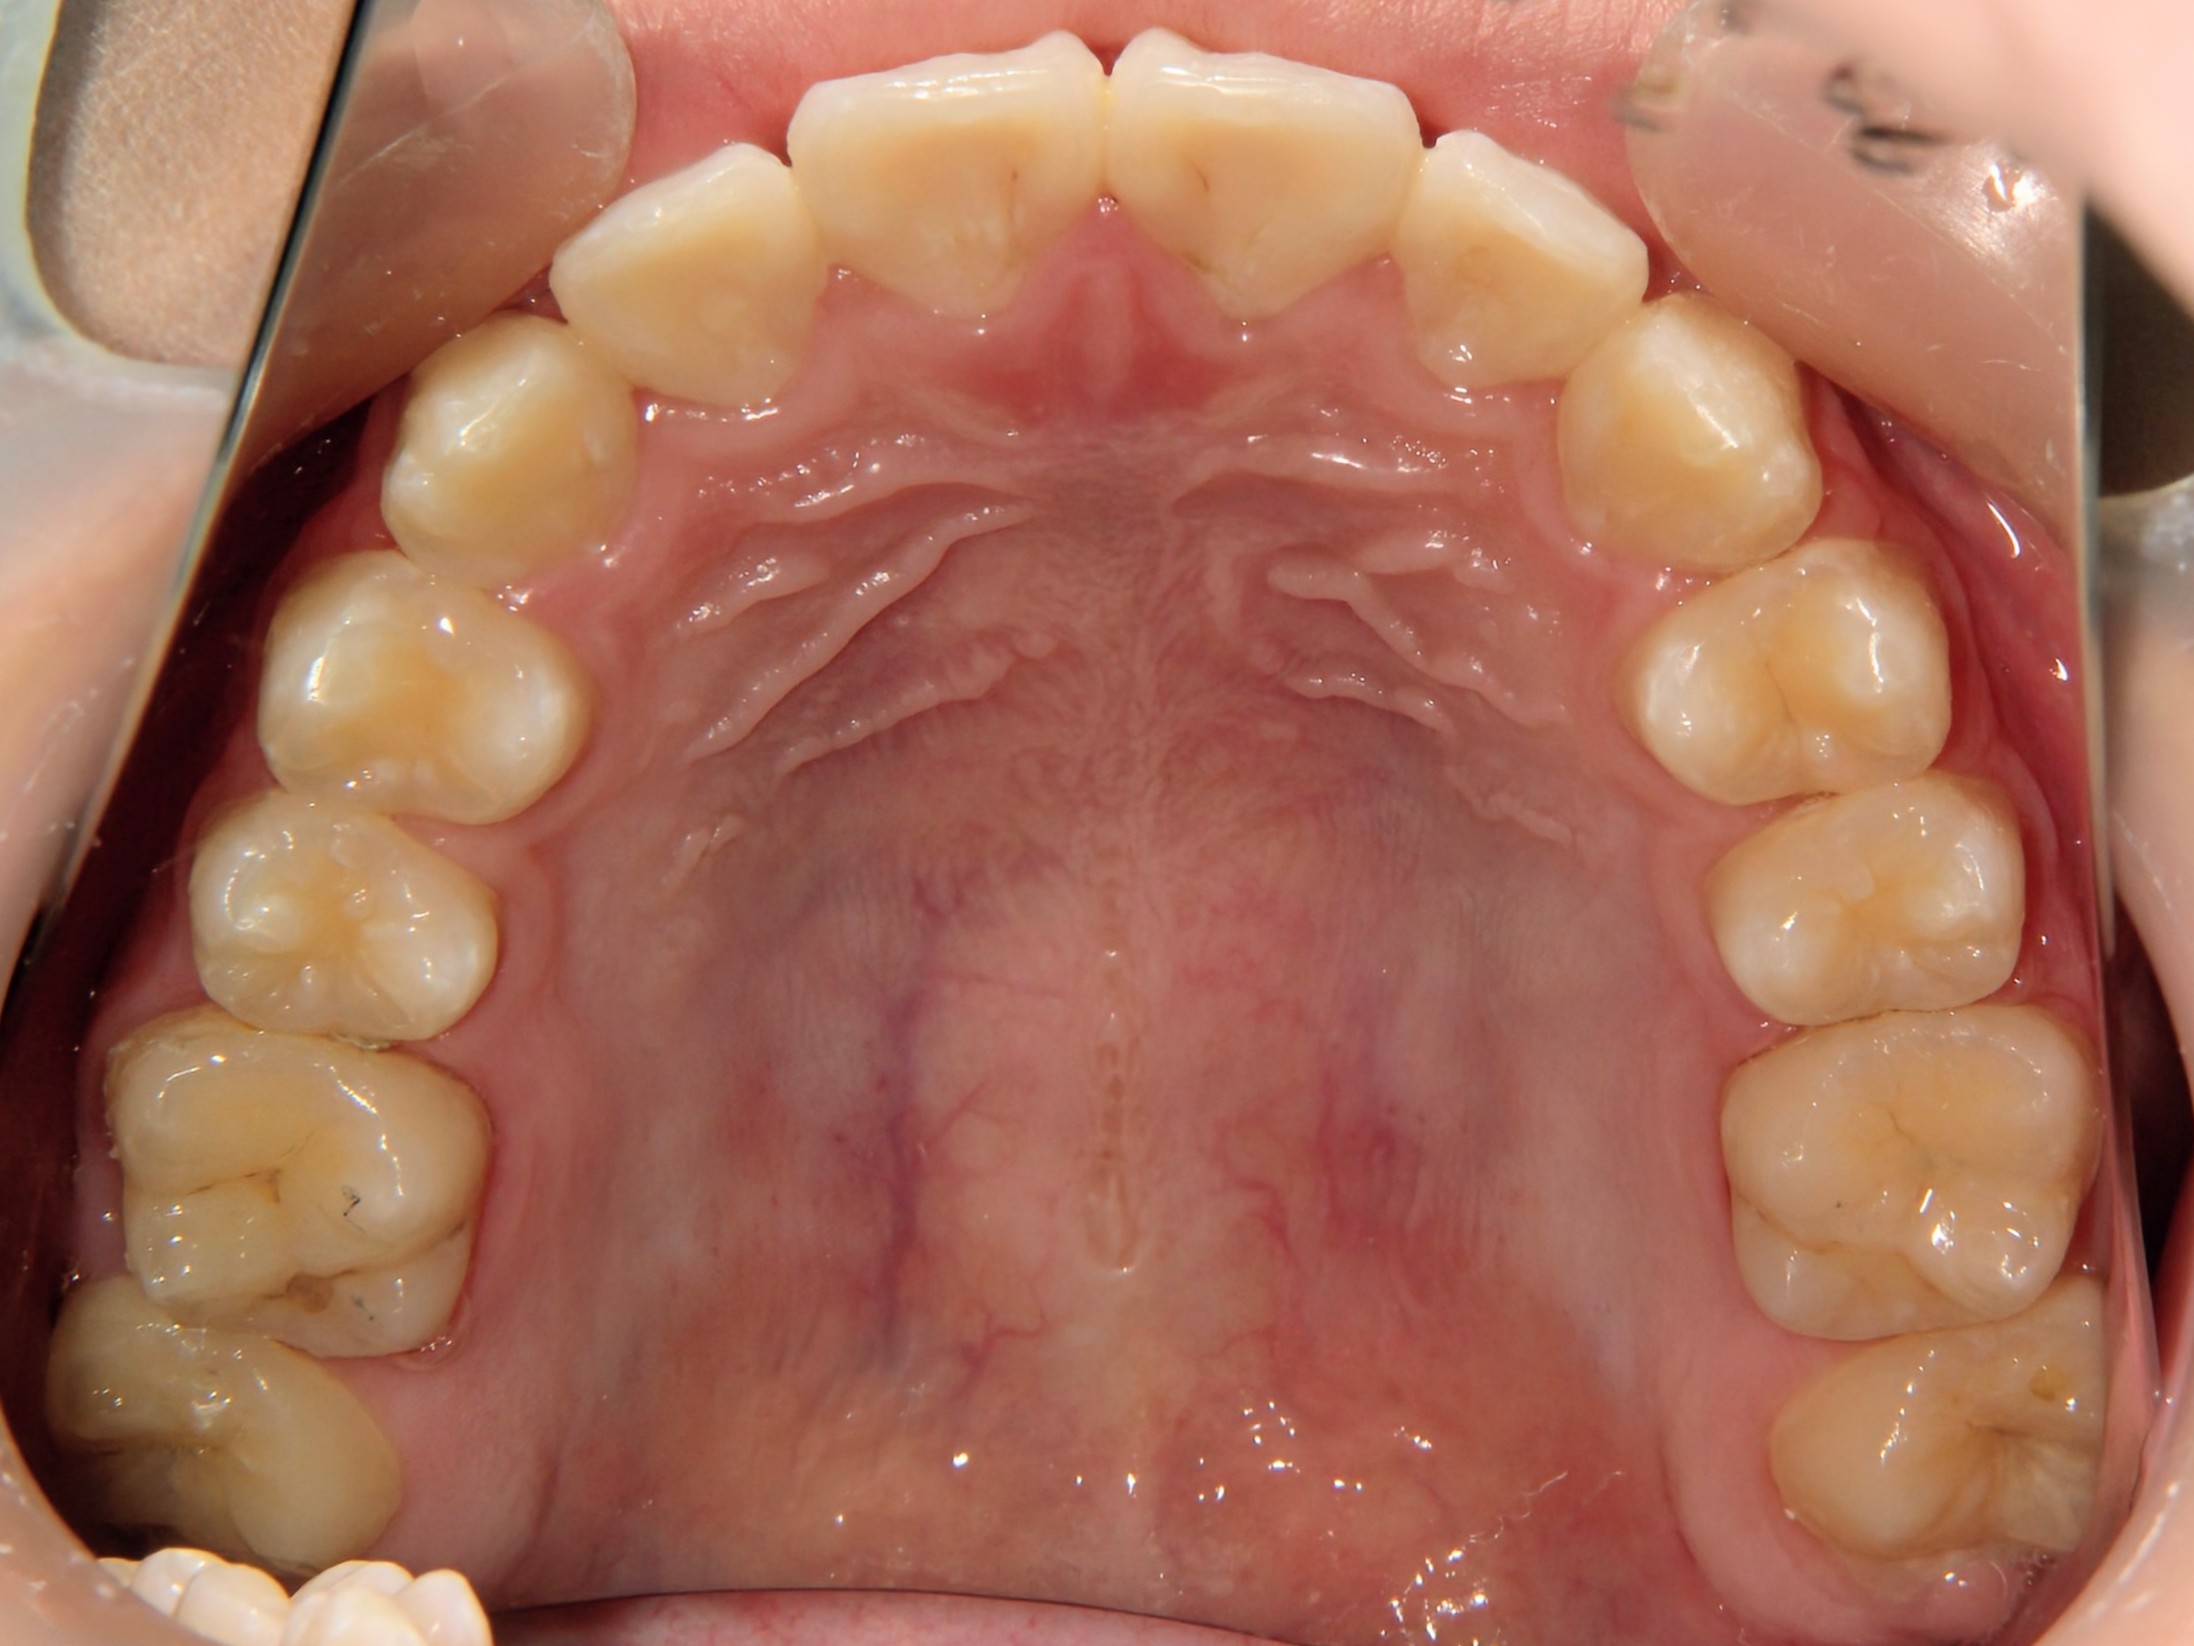

第2期治療開始時

口腔内写真

開始年齢

13歳

主訴(患者様のお悩み)

残りの歯のデコボコを治したい

診断

上下顎軽度の叢生(上下の歯のデコボコ)

上顎右側犬歯低位(右上の八重歯)

治療方針

非抜歯矯正治療

全体的に装置を装着し、歯のデコボコや咬み合わせを治療

使用装置

表側矯正装置

治療期間の目安:約1年~1年半(保定期間を除いた期間)